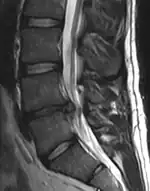

- Magnetic resonance imaging is the gold standard study for confirming a suspected LDH. With a diagnostic accuracy of 97%, it is the most sensitive study to visualize a herniated disc due to its significant ability in soft tissue visualization. MRI also has higher inter-observer reliability than other imaging modalities. It suggests disc herniation when it shows an increased T2-weighted signal at the posterior 10% of the disc. Degenerative disc diseases have shown a correlation with Modic type 1 changes. When evaluating for postoperative lumbar radiculopathies, the recommendation is that the MRI is performed with contrast unless otherwise contraindicated. MRI is more effective than CT in distinguishing inflammatory, malignant, or inflammatory etiologies of LDH. It is indicated relatively early in the course of evaluation (<8 weeks) when the patient presents with relative indications like significant pain, neurological motor deficits, and cauda equina syndrome. Diffusion tensor imaging is a type of MRI sequence used for detecting microstructural changes in the nerve root. It may be beneficial in understanding the changes that occur after herniated lumbar disc compresses a nerve root, and might help in differentiating the patients that need surgical intervention. In patients with a high suspicion of radiculopathy due to lumbar disc herniation, yet the MRI is equivocal or negative, nerve conduction studies are indicated.[44] T2-weighted images allow for clear visualization of protruded disc material in the spinal canal.

MRI scan of large herniation (on the right) of the disc between L4 and L5 vertebrae

A rather severe herniation of the L4–L5 disc